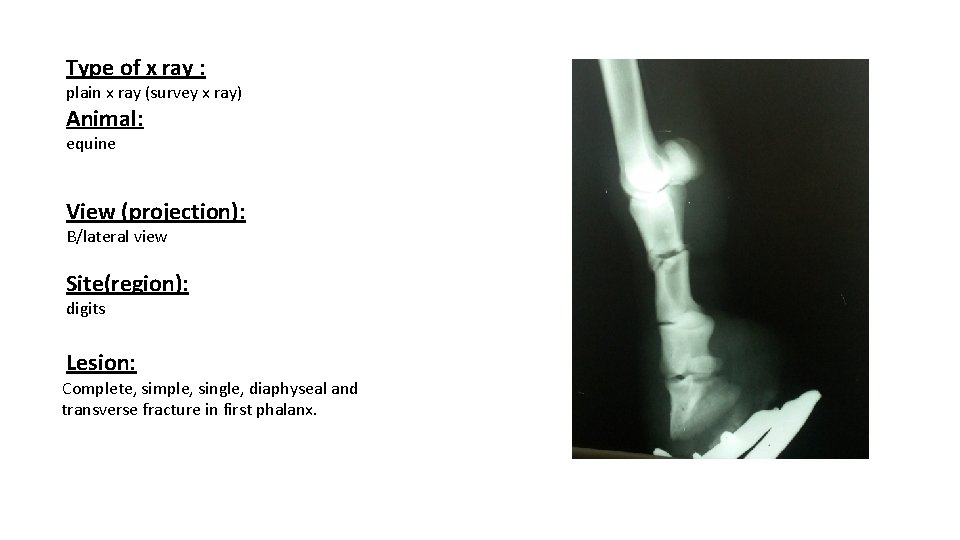

Type of x ray : plain x ray (survey x ray) Animal: equine View (projection): B/lateral view Site(region): digits Lesion: Complete, simple, single, diaphyseal and transverse fracture in first phalanx.